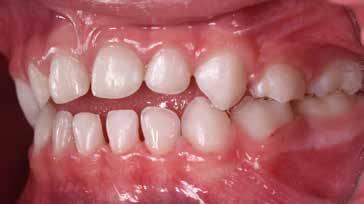

Presentazione del caso > F.V, bambino di cinque anni, presenta una malocclusione di II Classe scheletrica, III Classe dentale molare e canina destra e sinistra, morso inverso anteriore. Le arcate dentali mostrano usura degli elementi dentari anteriori a causa dell’occlusione patologica. Le linee mediane, superiore ed inferiore, sono centrate; il frenulo labiale superiore patologico per un’eccessiva estensione inter-incisale.

Dall’esame clinico si evince la III Classe dentale, l’inversione anteriore e l’over-jet negativo.

Una volta ottenuta la correzione del rapporto molare ed incisale, l’apparecchio elastodontico verrà portato dal paziente solo durante la notte per stabilizzare il risultato ottenuto e guidare l’eruzione degli elementi dentari per un totale di quattordici mesi di terapia. ad inizio trattamento :

Considerazioni > L’analisi cefalometrica ad inizio trattamento dimostra la II Classe scheletrica con protrusione del mascellare superiore e prognazia mandibolare; tendenza alla crescita verticale. L’esame clinico evidenzia una protrusione mandibolare funzionale.

55 54 ESTETICA FUNZIONE POSTURA Valori cefalometrici ad 1 anno di terapia : ANB ANB 3,8 Posizione del Mascellare SNA 91.40 Posizione della Mandibola SNB 87,60 Angolo Articolare SArGo 155,00 Angolo Goniaco ArGoMe 122,00 Angolo incisivo inf^Corpo madibolare IiMand 80,20 Angolo incisivo Sup^Base Cranica Ant. IsCran 111,05 Angolo Interincisivo II 138,00 72, 73 _ Over-bite e over-jet. 74 _ Immagine laterale destra. 75 _ Immagine laterale sinistra. Considerazioni > La terapia precoce di tali malocclusioni è di primaria importanza in quanto impedisce la formazione di malocclu-